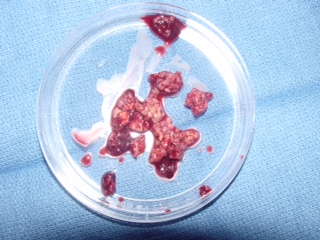

Gross (Fig. 8)

• Dependent on amount of lipid, fibrous tissue, and hemorrhage

• May be gray, yellow, white, or red

• Soft or firm

Fig. 8: Gross Pathology of a benign fibrous histiocytoma demonstrates multiple pieces of grayish fibrous tissue.